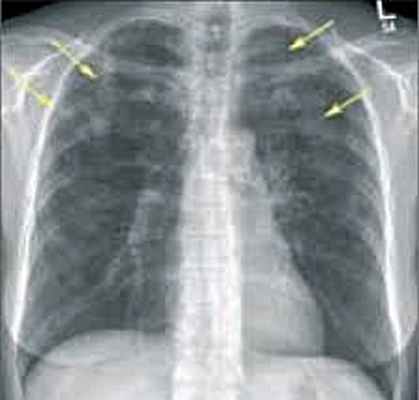

- Рентгенография легких. На снимках видны субплеврально расположенные одиночные (реже множественные, двусторонние) нечеткие затемнения средней интенсивности неправильной формы размером до 3-4 см. В окружении инфильтрата легочный рисунок усилен, тень корня легкого слегка расширена. Характерна быстрая динамика инфильтратов с миграцией по легочным полям и исчезновением не позднее 1-2 недель после обнаружения (чаще через 1-3 дня) без остаточной рубцовой деформации. При длительно поддерживающемся инфильтративном воспалении в ткани легких могут образоваться фиброзные очаги и кистозные полости.

Острая эозинофильная пневмония - может быть идиопатической (без установленной причины), либо ассоциированной со СПИДом, приёмом медикаментов, ингаляцией бытовых и промышленных поллютантов (продукты жизнедеятельности человека токсического характера), табачного дыма. Чаще всего развивается у мужчин 20-30 лет. Характеризуется острым началом с лихорадкой, выраженной одышкой, кашлем без мокроты. В тяжёлых случаях возможно развитие дыхательной недостаточности. На рентгенограммах, на КТ легких определяется диффузная инфильтрация с обеих сторон. Эозинофилия в крови часто отсутствует, но всегда обнаруживается в БАЛ.

На рентгенограммах и КТ определяются участки инфильтрации различной плотности, расположенные по периферии, как правило, в верхних долях лёгких. В анализах крови выявляются значительное увеличение общего IgE, воспалительные изменения: повышение СОЭ, С-реактивного белка. Эозинофилия в крови определяется не всегда, но в БАЛ превышает 25%. В отличие от острой эозинофильной пневмонии длительность заболевания более 2 мес., возможны рецидивы.